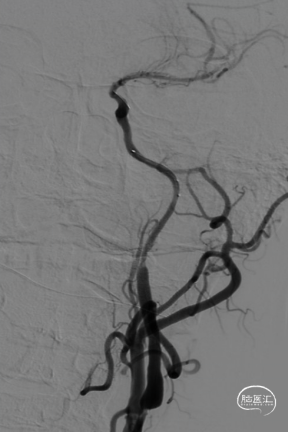

回撤SKATHI远端通路导管至C3段,通过导管再次释放SPIDER保护伞,回撤导管至颈总动脉,造影见C1段严重狭窄,以4-30mm球囊扩张狭窄段,复查造影狭窄段好转,远端再次闭塞,考虑斑块或血栓脱落,立即置入7-40 wallstent支架。

复查造影远端仍然闭塞,负压状态上行SKATHI远端通路导管回收保护伞并抽吸血栓,可见保护伞及大量血栓取出,复查造影C3段仍有血栓。再次上行SKATHI远端通路导管抽吸取栓,复查造影示远端血流通畅。

等待10分钟,复查造影颈内动脉及远端分支通畅,结束手术。DynaCT左侧外囊区域少许造影剂渗出。